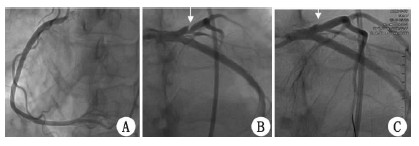

2.4 冠脉造影7例患者外伤恢复后均接受冠脉造影检查,其中4例患者冠脉造影可见前降支近段夹层,1例患者见回旋支近段夹层,以上5例患者行经皮冠状动脉介入治疗(PCI),在病变血管夹层处植入支架。1例患者冠脉造影见前降支中段血管局部轻度狭窄,1例患者冠脉造影结果正常,未进一步行PCI治疗。

| A:右冠状动脉;B:前降支夹层;C:前降支支架植入后 图 1 例6 患者血管造影及PCI术后造影图 |